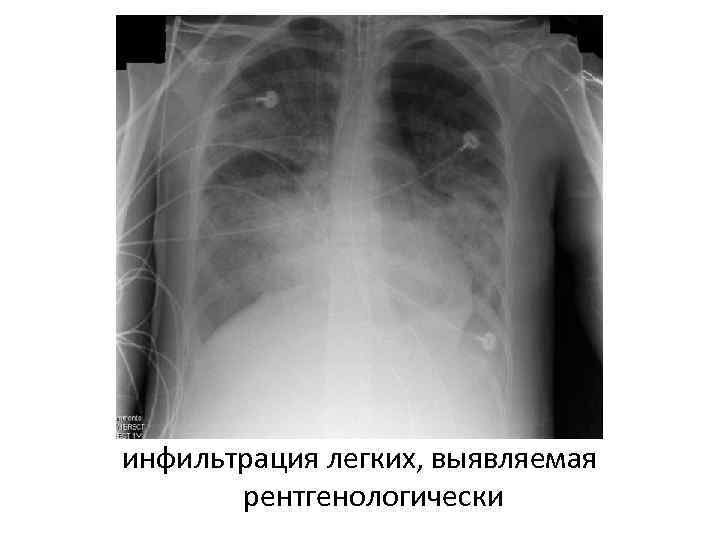

Респираторный дистресс-синдром(РДС) РДС (пример острой дыхательной недостаточности) - полиэтилогическое состояние, характеризующееся острым началом, выраженной гипоксемией (не устраняемой оксигенотерапией), интерстициальным отеком и диффузной инфильтрацией легких. РДСВ может осложнять любое критическое состояние, вызывая тяжелейшую острую дыхательную недостаточность. Несмотря на прогресс в диагностике и лечении данного синдрома, летальность составляет 50%, по некоторым данным - 90%.

Проявление • клинические и лабораторные (ра. О 2 <55 мм рт. ст. ) признаки гипоксии, некупируемой ингаляцией кислородом • Одышка. Для дистресс-синдрома характерно тахипноэ. • Увеличение МОД. • Уменьшение лёгочных объёмов (общей ёмкости лёгких, остаточного объёма лёгких, ЖЁЛ, функциональной остаточной ёмкости лёгких). • Гипоксемия, острый дыхательный алкалоз. • Увеличение сердечного выброса (в терминальной стадии синдрома — снижение). • Кроме того, при РДСВ отмечаются интерстициальный отек, ателектазы, в сосудах легких - множество мелких тромбов (гиалиновых и фибриновых), жировые эмболы, гиалиновые мембраны в альвеолах и бронхиолах, стаз крови в капиллярах, внутрилегочные и субплевральные кровоизлияния.

инфильтрация легких, выявляемая рентгенологически